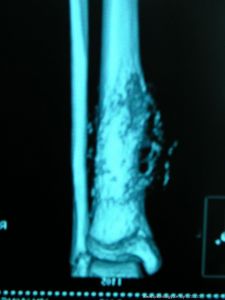

軟組織腫瘤影像(三)X線攝片檢查X線攝片有助於進一步了解軟組織腫瘤的範圍,透明度以及其與鄰近骨質的關係。如邊界清晰,常提示為良性腫瘤;如邊界清楚並見有鈣化,則提示為高度惡性肉瘤,該情況多發生於滑膜肉瘤、橫紋肌肉瘤等。

外科專家介紹了軟骨肉瘤發病早期的一些症狀,提示廣大青少年,如有以下症狀要及時到醫院進行檢查:1、早期患者的患病區域會感覺不適,幾天或幾周后出現腫脹及腫塊,晚期可出現靜脈曲張,局部皮膚溫度升高及充血發紅。2、一般患者會感覺關節周圍疼痛,最初是間歇性疼痛,一段時間後逐漸加重,轉為持續性疼痛,夜間更為明顯,服用止痛藥無效。3、患者的關節活動受限,有些病人會發生關節積液,甚至會發生病理性骨折。飲食護理